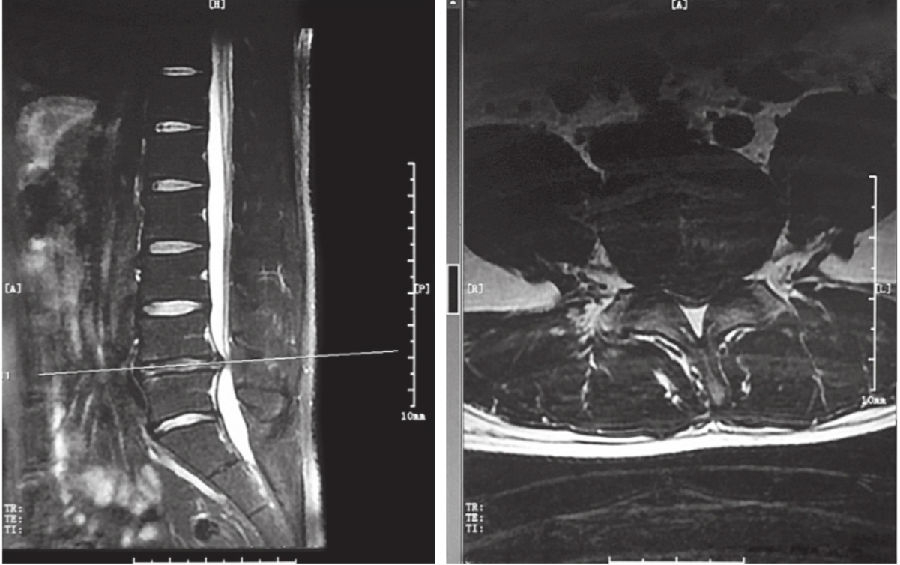

纤维环完全破裂,髓核突向椎管,仅有后纵韧带或一层纤维膜覆盖,表面高低不平。此类型常需手术治疗。(图1)

3. 脱垂游离型

破裂突出的椎间盘组织或碎块脱入椎管内或完全游离。此型容易导致马尾神经症状,常需手术治疗。(图2)

图1 腰椎磁共振显示中央突出型的L4-5椎间盘

图2 腰部磁共振显示脱垂游离型的L5-S1椎间盘